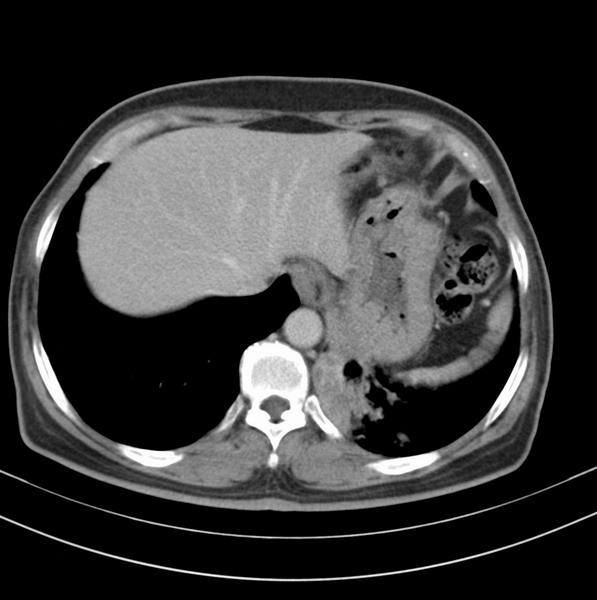

标题: CT20053:胸部增强请会诊。

女、63

咳嗽、胸痛四个月

考虑左下肺中央型肺癌

支持左下中央型肺癌伴阻塞性炎症不张。

包绕左下肺基底段的不规则的软组织肿块,段支气管腔变形、狭窄及阻塞性炎症,病变区不规则强化,又是老年女性支持楼上看法。

典型病例:左下肺基底段中央型肺癌,相应支气管狭窄并阻塞性炎症